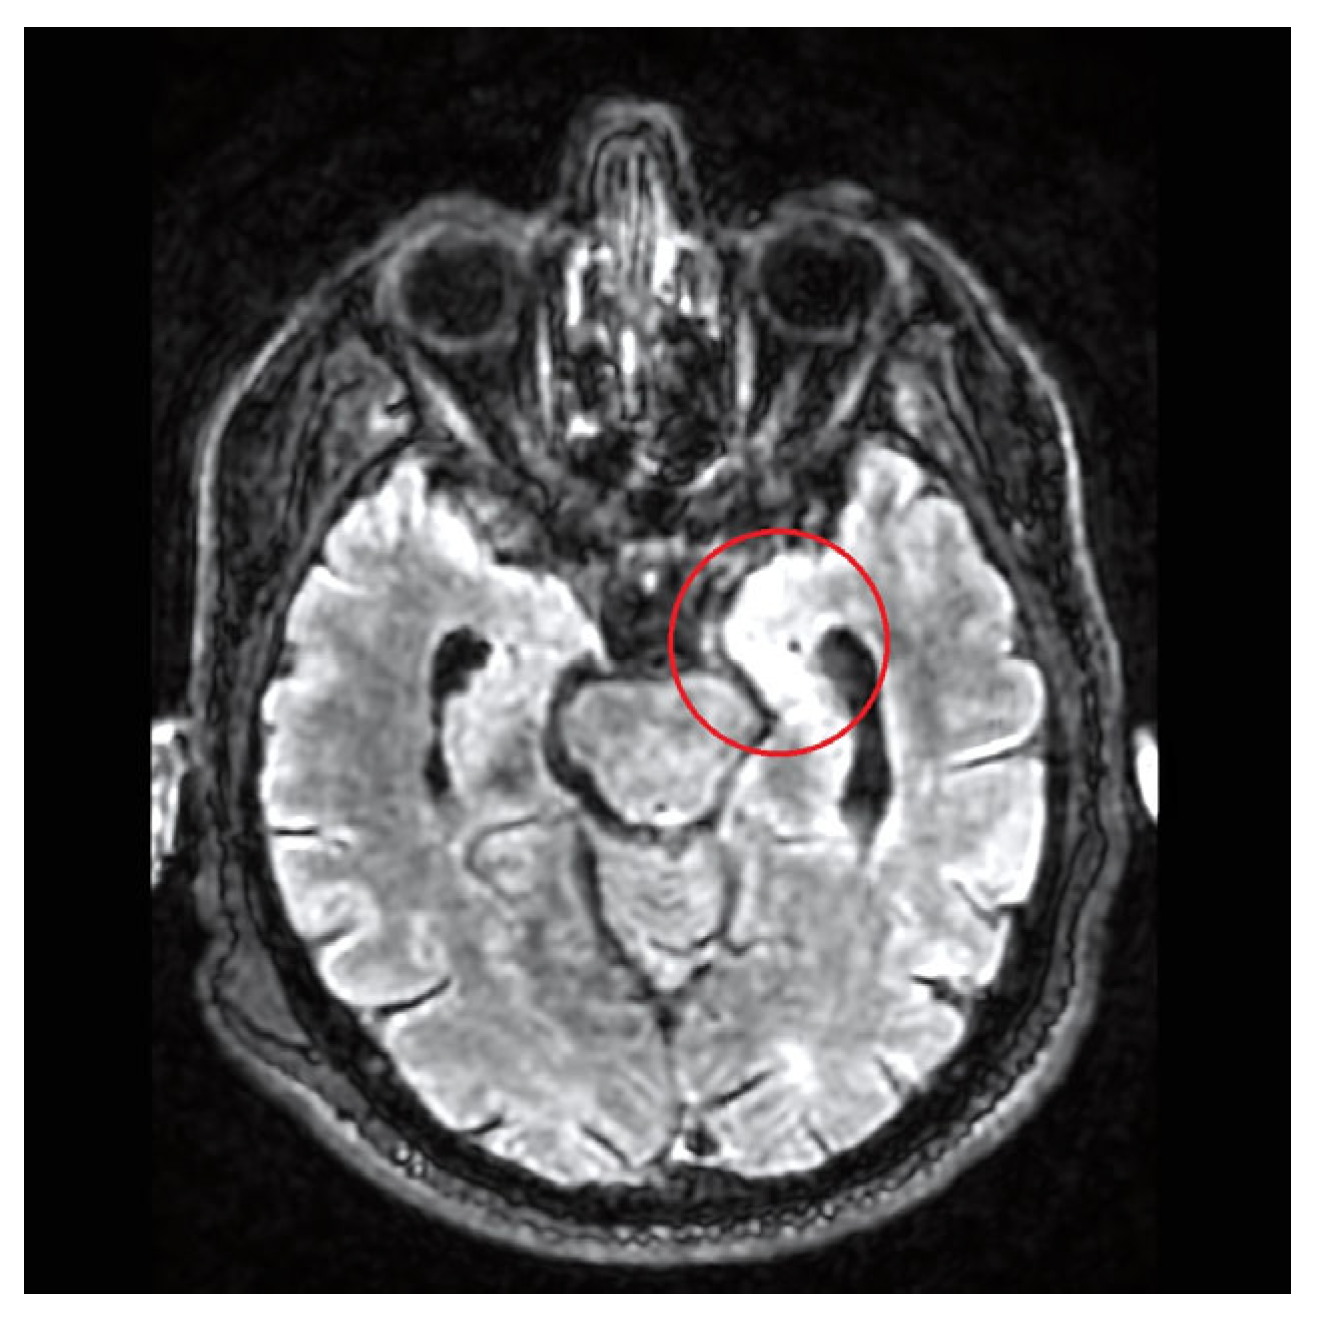

| 8 | Our case | 77/M | Fever, confusion | Right frontal lobe hyperintensity and left lateral ventricle exclusion. | Encephalitis and ventriculitis | CSF | Pleocytosis, hypoglycorrhachia, and hyperproteinorrachia | INH + RIF + EMB + LEV; LIN (2 weeks) | No | Yes | 14 | SR |